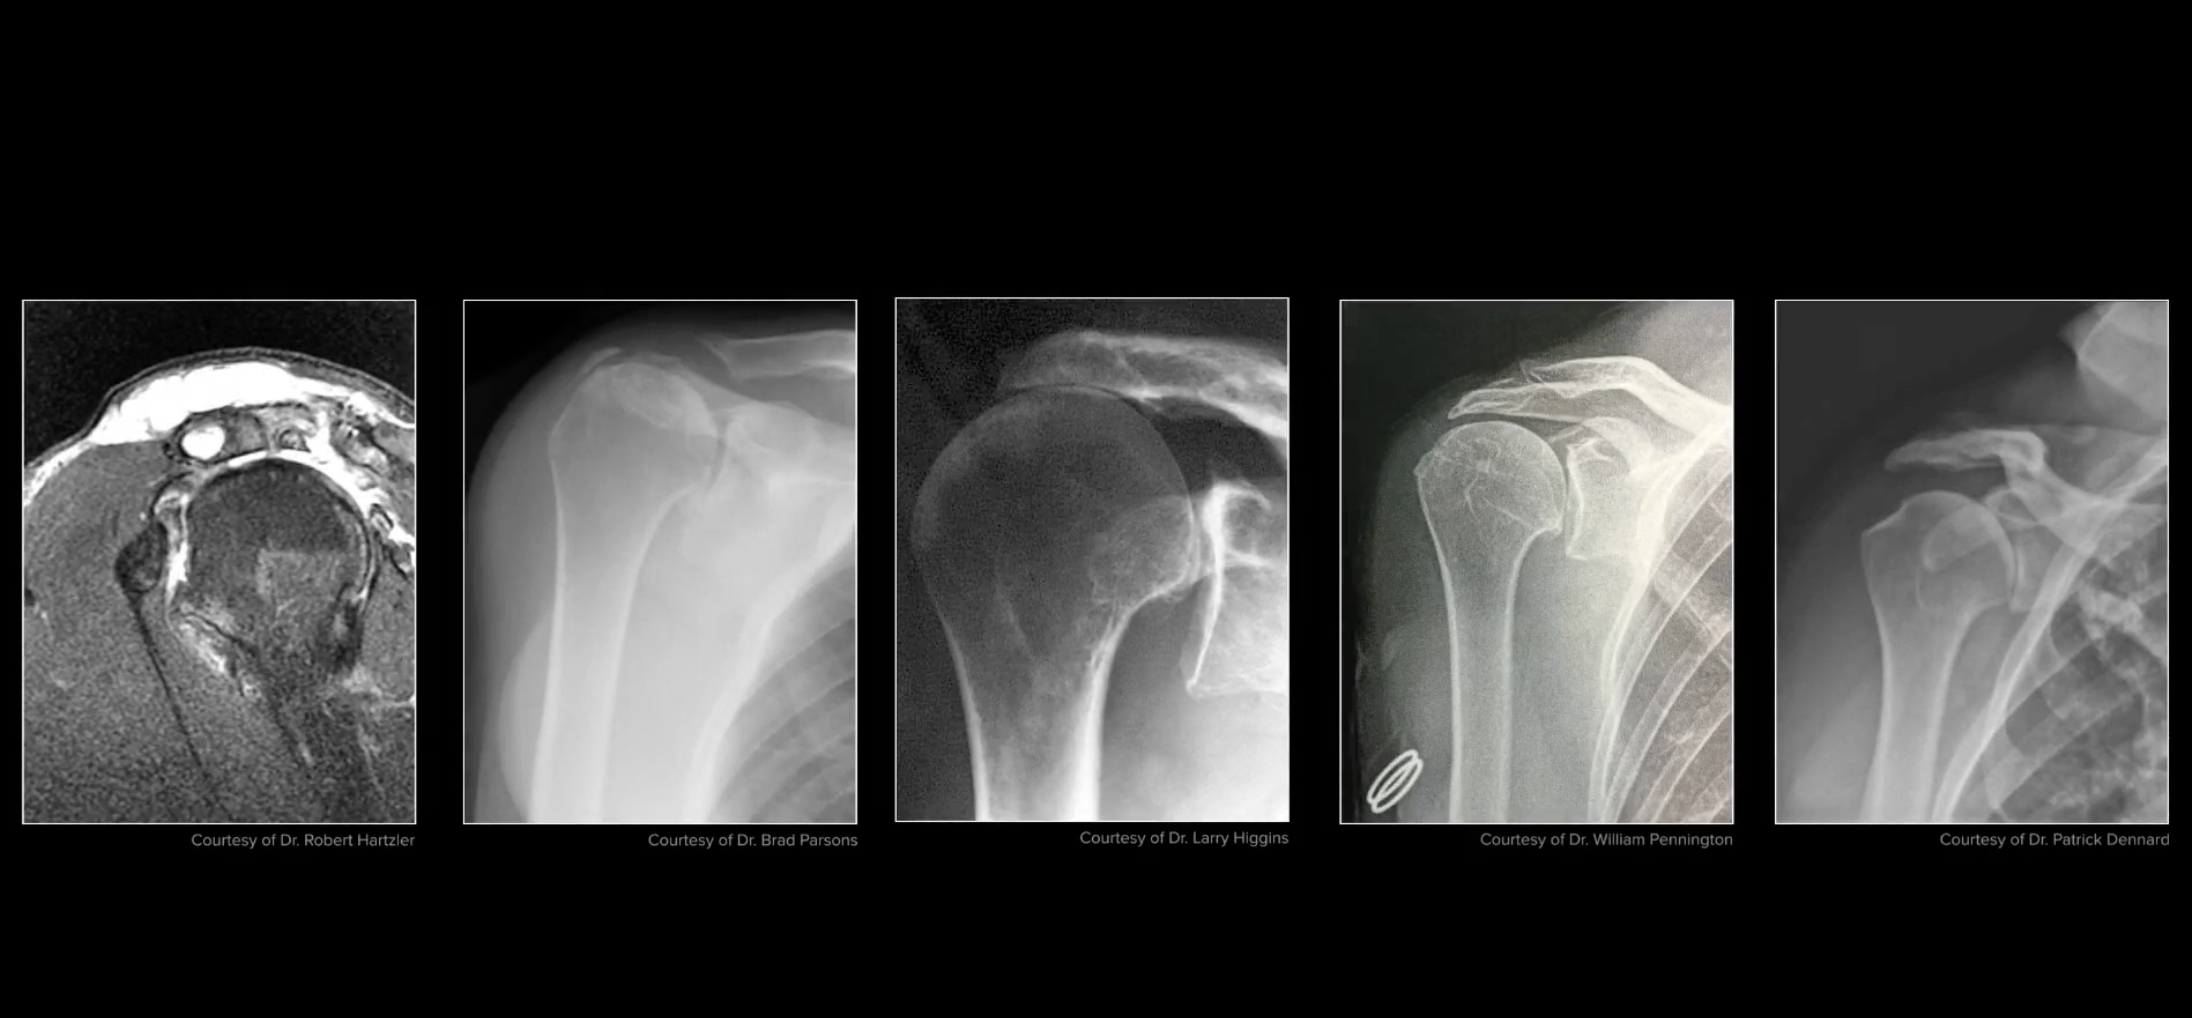

Rotator Cuff Tear Arthropathy Shoulder Arthritis shoulder surgeon Rotator Cuff Tear Arthropathy Icd 10 Etiology, natural history, anatomy, clinical evaluation, xray / diagnostic tests, classification / treatment, associated injuries /. — this review provides an overview on the diagnostic criteria, classification, pathoanatomic changes,. — rotator cuff arthropathy is a specific pattern of shoulder degenerative joint disease that results from a rotator. rotator cuff tear arthropathy is a spectrum of degenerative disease. Rotator Cuff Tear Arthropathy Icd 10.

Rotator cuff tear arthropathy. (a) Conventional Xray, (b Rotator Cuff Tear Arthropathy Icd 10 rotator cuff tear arthropathy rapidly destructive shoulder joint and bone disease found mainly in elderly, and predominantly in women. rotator cuff tear arthropathy is a spectrum of degenerative disease that develops due to a rotator cuff deficient shoulder. — this review provides an overview on the diagnostic criteria, classification, pathoanatomic changes,. — rotator cuff arthropathy is. Rotator Cuff Tear Arthropathy Icd 10.